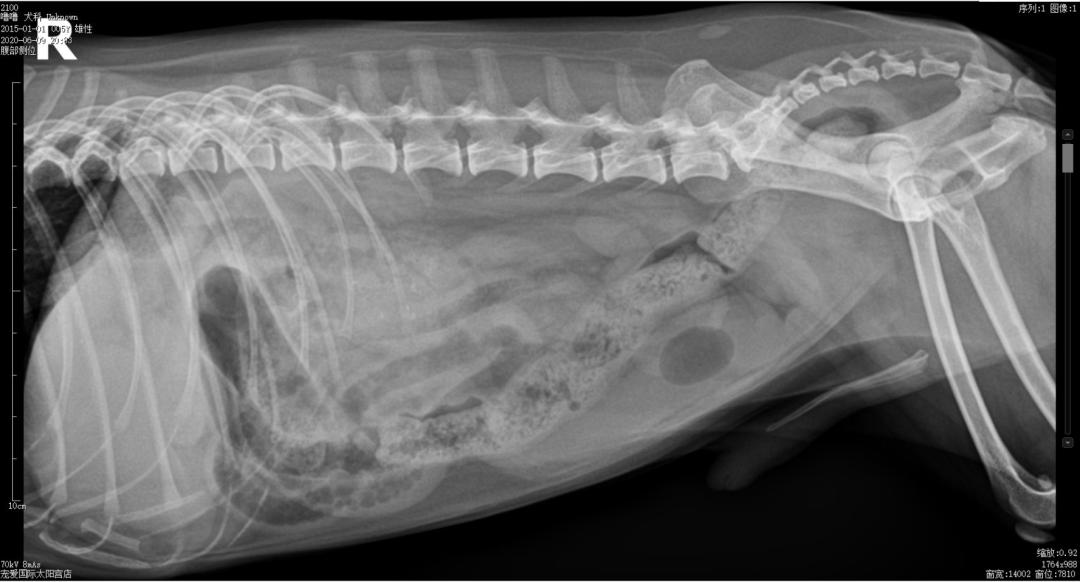

X光检查↓↓

杆状升高,C反升高,提示机体存在炎症,淀粉酶下降无实际意义,DR检查小肠前段有扩张和积气,未见明显异物,结合临床症状及辅助检查,初步怀疑肠道异物。